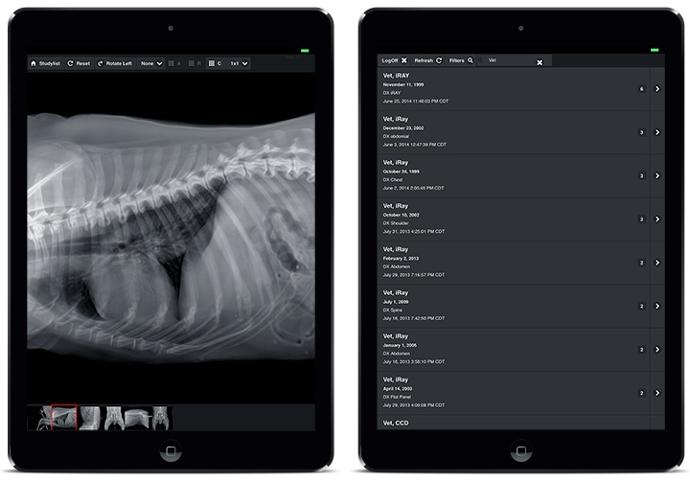

Système radiographique vétérinaire VETSMART DR